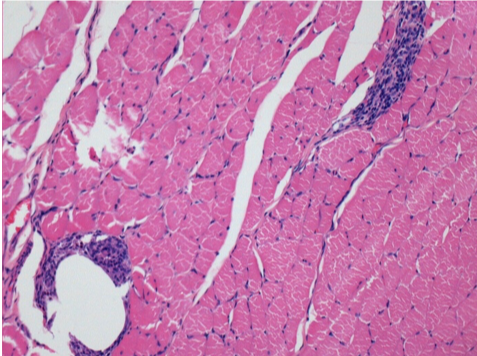

7 місяців (210 днів) після ін'єкції 0,1 мл Ендопіл в правий претибіальний м'яз.

Повна Restitutio ad integrum через 7 місяців

Л :Контроль 50x210 днів

П:50X-210 днів